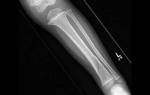

- рентген ребер и грудной клетки;